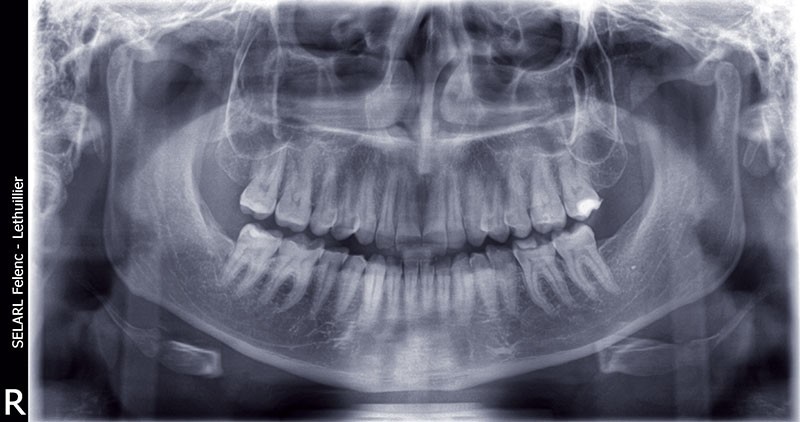

L’examen radiologique ne révèle aucune perte osseuse interproximale, ni de lésions endodontiques (fig. 8).